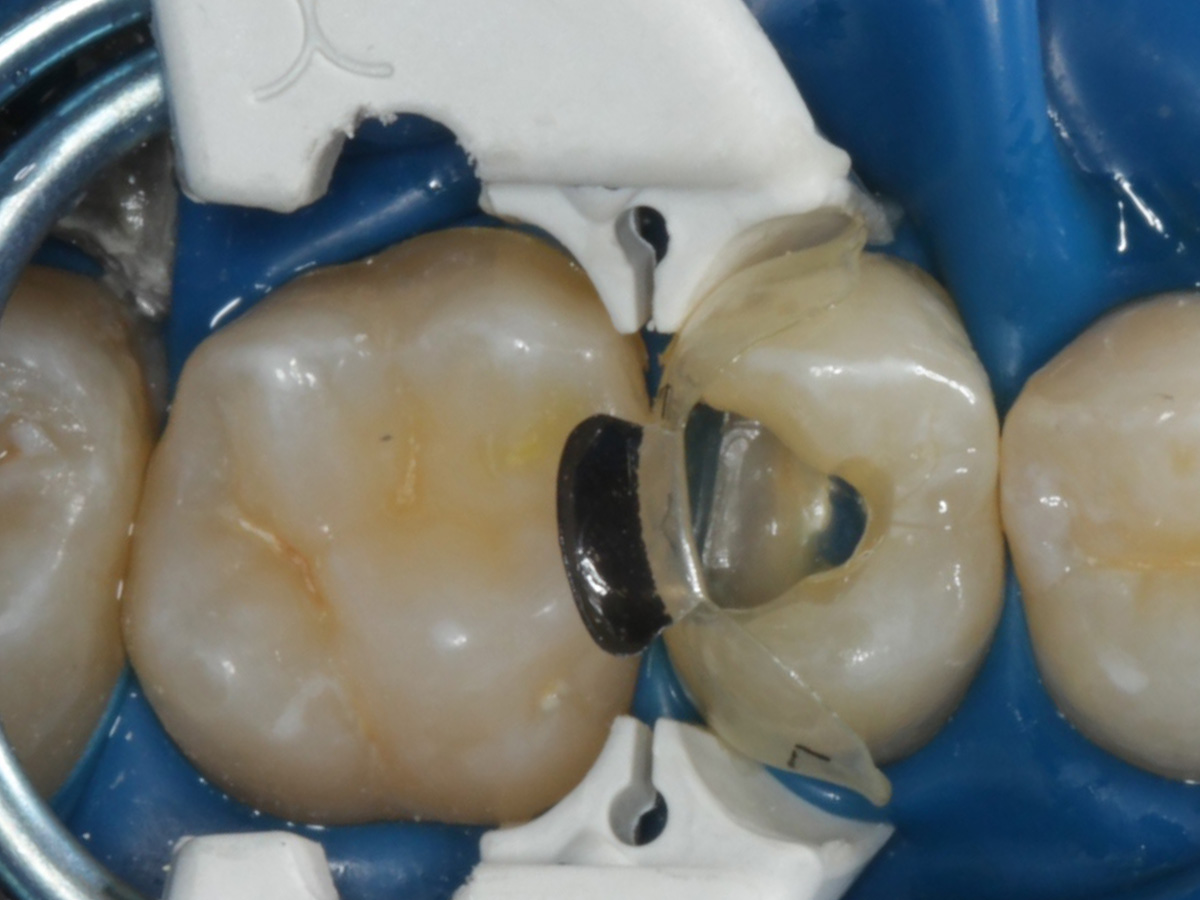

Abbildung 24

Folgesitzung: Trepanation Zahn 25

Abbildung 25

Nadelaufnahme nach elektronischer Längenmessung